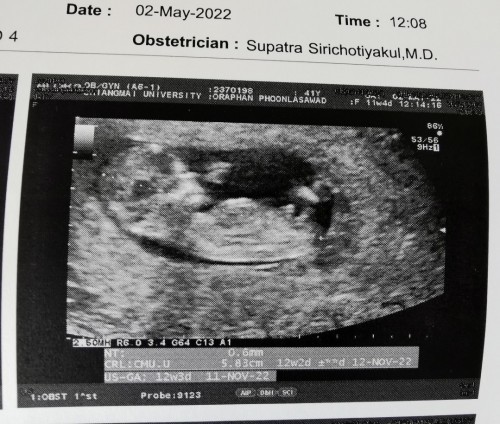

ภาพอันตร้าซาวด์ติน5เดือนใครเป็นแบบนี้บ้างคะ

ภาพ ซาวตอน5เดือน มีใครเหมือนบ้านนี้มั้ยคะ ในถาพน้องจะท้องใหญ่ แต่คุณหมอไม่ได้แต้งอะไรค่ะ เป็นปกติมั้ยคะ มีอม่ๆคนไหนเป็นเหมือนกันบ้างคะ

12 สัปดาห์ค่ะ

11w5d ค่ะ